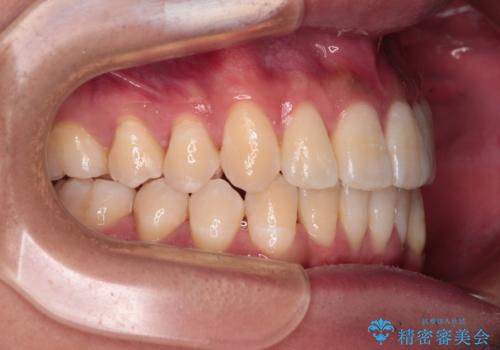

歯列としてはインビザラインでもワイヤー矯正でも対応できるものでしたが、上顎の八重歯や下顎小臼歯の捻転といったインビザラインでは時間のかかってしまう歯列不正が認められたため、補助装置やワイヤー矯正を治療当初に使用することで、インビザラインによる治療をスムーズに行えるように計画しました。

インビザラインは得意・不得意の差がはっきりとしているため、ワイヤー装置などをうまく活用することで、治療期間を短縮するとともに、より理想的な仕上がりを達成することができます。